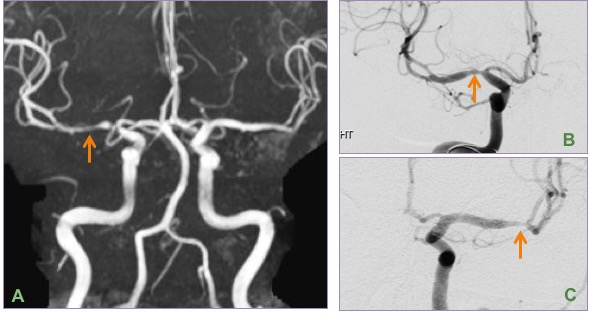

MIP image from MR angiogram (A) shows beaded narrowing of the right M1 segment. DSA images (B & C) confirm the finding seen on the MRA with narrowing of bilateral M1 segments, more pronounced on the right side (side of the infarct).

The etiology of this entity is unknown as the vasospasm and infarct can occur even in say the anterior circulation vessels despite it being a posterior fossa surgery (it is not related to direct surgical handling or trauma). It is more commonly seen after skull base surgeries in the posterior fossa. Vessel irregularities are seen on MRA/DSA.